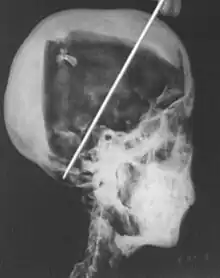

- 1968; A portable X-ray machine was used to examine the mummy of Tutankhamun in his tomb in the Valley of the Kings by researcher R. G. Harrison. These images indicated an age of death of around 18–20 years based on bone age from a study of the limb lengths, as well as tooth analysis. The rumoured cause of death of tuberculosis was also ruled out during this study. A new hypothesis was formed that Tutankhamun died because of blunt force trauma to the head, due to a depressed fracture found on the skull.[6]

A recent CT scan of Tutankhamun in 2006 was able to provide evidence against the 'homicide theory'.[2][6] A depression fracture noted on the skull from X-rays taken 30 years previously was found to be a post-mortem injury rather than a cause of death.[6] The hole in the head had been created in order to continue the embalming process of mummification.[10] This CT investigation was also able to confirm Tutankhamun's age of death as nineteen and disprove the idea that the young pharaoh had suffered from scoliosis; rather the bend in his spine was from additional post-mortem damage to the body.[10]